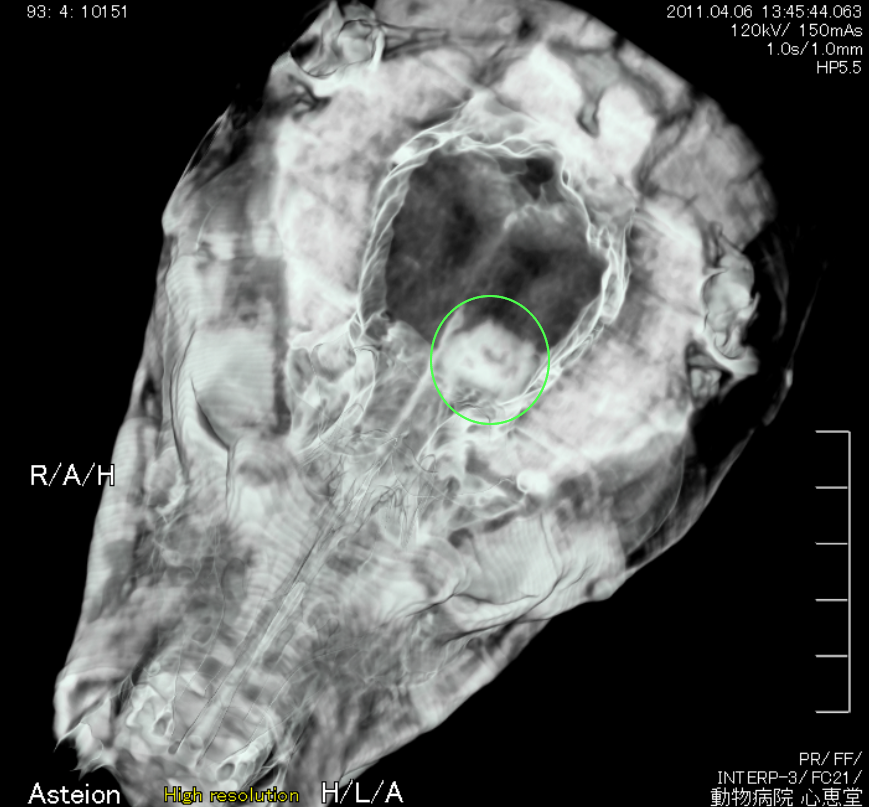

• 頭部病変

• 鼻腺癌による骨融解像 脳腫瘍

鼻腺癌による骨融解像 脳腫瘍